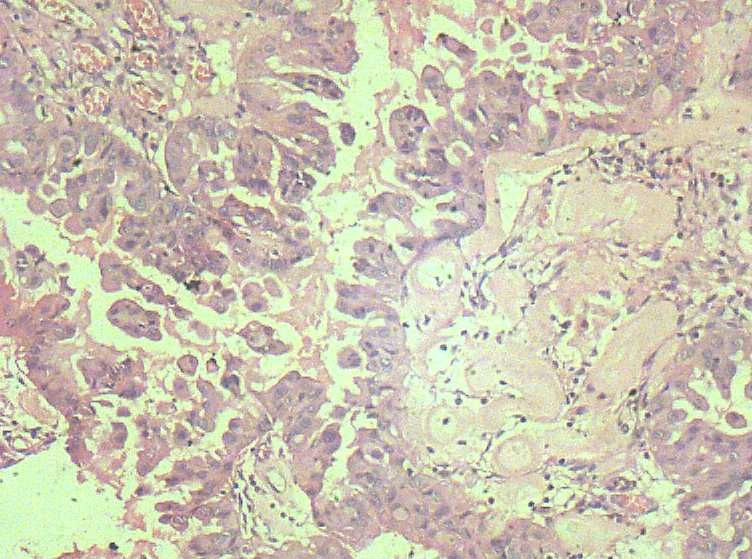

女,27岁,剖宫产术中见一侧卵巢一肿物。大体:椭圆形肿物大小3*2*1.5表面光滑,剖开内容为浅黄色胶状物,质均,囊内壁较光滑,部分见细小乳结构。

• 卵巢交界性浆液性囊腺瘤?图1

图1

那这例还真不好下诊断了 组织学已到了交界 但又不得不考虑妊娠的因素。这样的标准究竟是什么?本人感觉是个良性的 但组织学又到了交界 真不知道如何下诊断 要不下个 病变符合交界性?

有乳头的部位 基本都有取到了 。看来报个交界性不是问题了。谢谢各位老师的意见!